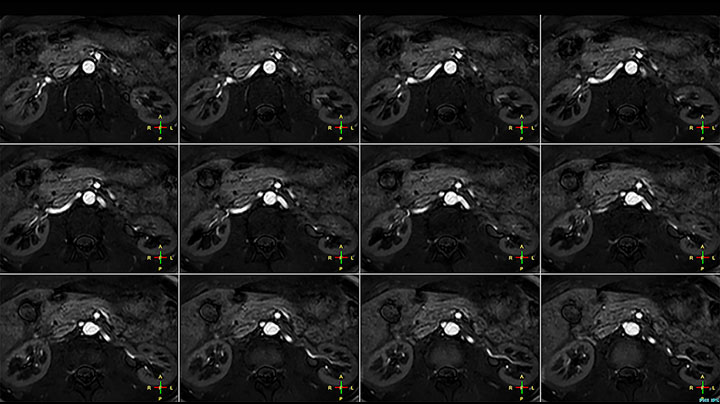

Obgleich die Region zwischen Hals und oberer Lungenspitze für ein MR-System einer der schwierigsten Bereiche ist, ergeben die mit Prodiva 1.5T erfassten Bilder bei diesem 56-jährigen Mann mit einem Pancoast-Tumor rechts eine gute Qualität. mDIXON TFE Bilder zeigen eine hervorragende Fettsuppression im Halsbereich und die diffusionsgewichtete Bildgebung enthält fast keine Verzerrungen.